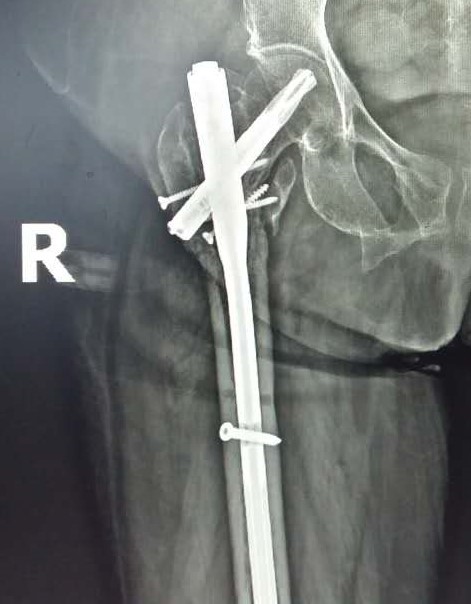

股骨转子间骨折术后内固定断裂

翻修术后一年